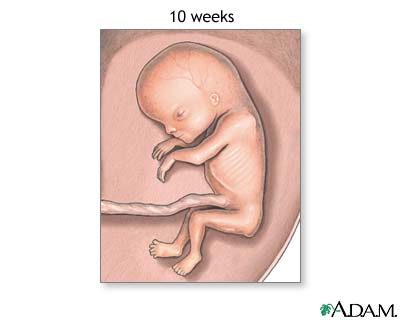

Weeks 11 to 14

- Your baby's eyelids close and will not reopen until about the 28th week.

- Your baby's face is well-formed.

- Limbs are long and thin.

- Nails appear on the fingers and toes.

- Genitals appear.

- Your baby's liver is making red blood cells.

- The head is very large -- about half of your baby's size.

- Your little one can now make a fist.

- Tooth buds appear for the baby teeth.